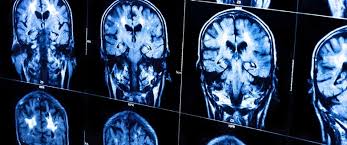

O diferencial do NeuroUPC, inaugurado no dia 12 de agosto, cujas 16 salas ocupam um espaço de 300 metros quadrados do hospital, são os aparelhos disponíveis para o estudo das neuropatias de fibras finas. Essas neuropatias podem ocorrer em pacientes com hanseníase, diabetes, doença de Parkinson e esclerose múltipla, entre outras patologias.

“Os exames convencionais para mensurar lesões no sistema nervoso periférico, como a eletroneuromiografia, não conseguem avaliar as atividades das fibras finas, responsáveis pela sensação de dor. A avaliação médica da dor nesses pacientes, portanto, dependia das informações passadas por eles, o que a tornava subjetiva e gerava, eventualmente, diagnósticos imprecisos”, ressalta o neurologista coordenador da Unidade, Osvaldo Nascimento. Agora, com aparelhos como o Cheps, é possível avaliar a dor independentemente da opinião do paciente.